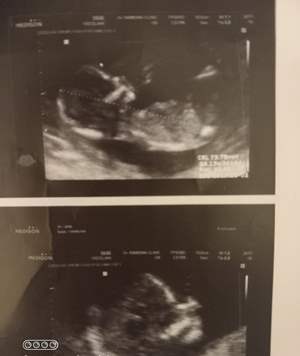

تو ۱۴ هفته ام، سونوگراف گفت پشتش به مانیتوره ولی بنظرم دختره